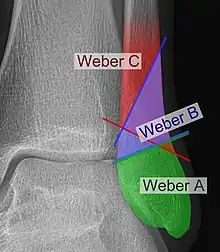

The Danis–Weber classification (often known just as the Weber classification) is a method of describing ankle fractures. It has three categories:[1]

- Type A

Fracture of the fibula distal to the syndesmosis (the connection between the distal ends of the tibia and fibula). Typical features:

- below level of the ankle joint

- tibiofibular syndesmosis intact

- deltoid ligament intact

- medial malleolus occasionally fractured

- usually stable: occasionally nonetheless requires an open reduction and internal fixation (ORIF) particularly if medial malleolus fractured

- Type B

Fracture of the fibula at the level of the syndesmosis. Typical features:

- at the level of the ankle joint, extending superiorly and laterally up the fibula

- tibiofibular syndesmosis intact or only partially torn, but no widening of the distal tibiofibular articulation

- medial malleolus may be fractured or deltoid ligament may be torn

- variable stability

- Type C

Fracture of the fibula proximal to the syndesmosis. Typical features:

- above the level of the ankle joint

- tibiofibular syndesmosis disrupted with widening of the distal tibiofibular articulation

- medial malleolus fracture or deltoid ligament injury present

- unstable: requires ORIF

Categories B and C imply a degree of damage to the syndesmosis itself (which cannot be directly visualised on X-ray). They are inherently unstable and are more likely to require operative repair to achieve a good outcome. Type A fractures are usually stable and can be managed with simple measures, such as a plaster of paris cast.